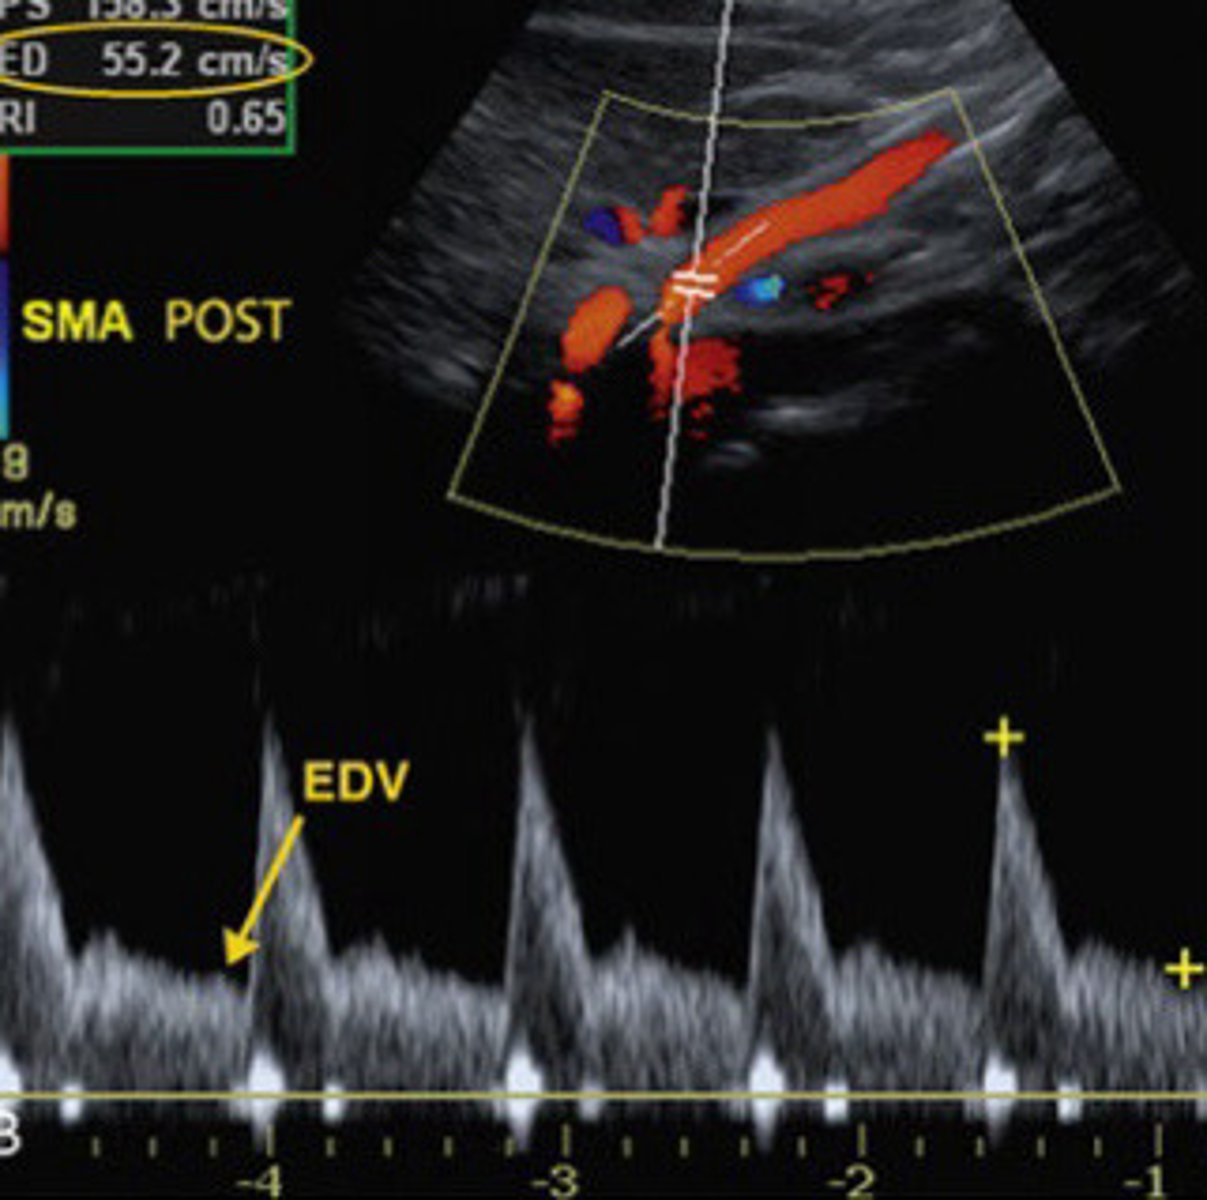

Low resistance (will probably be monophasic)

Describe the waveform of the SMA when the patient is in a post prandial state

What is the normal PSV seen in the SMA when the patient is in a post-prandial state

Post-prandial

Is this image taken form the SMA most likely from a patient who is pre-prandial or post-prandial

Lower resistance, PSV pretty much doubled and ESV pretty much tripled (compared to the pre-prandial waveform)

Describe the normal waveform post-prandial